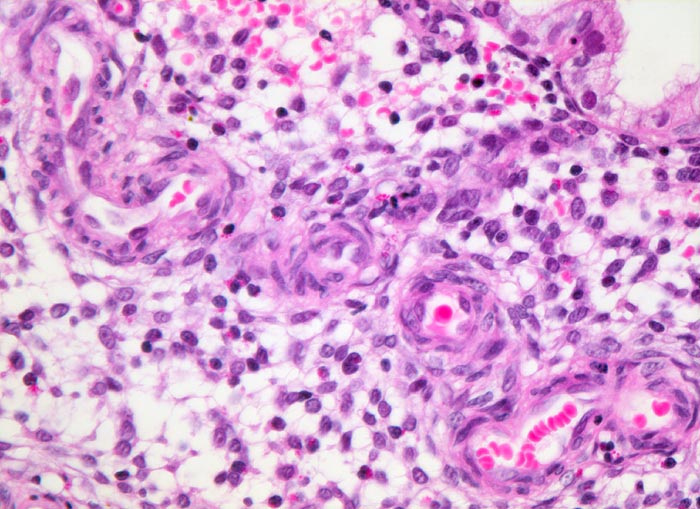

Endometrium in Sekretionsphase: Spiralarterien

Ödematöses Stroma mit prominenten gewundenen Spiralarterien. Das angrenzende Stroma ist ödematös. Es enthält

Körnchenzellen mit rotem Zytoplasma. Das Epithel der endometranen Drüsen ist einreihig.